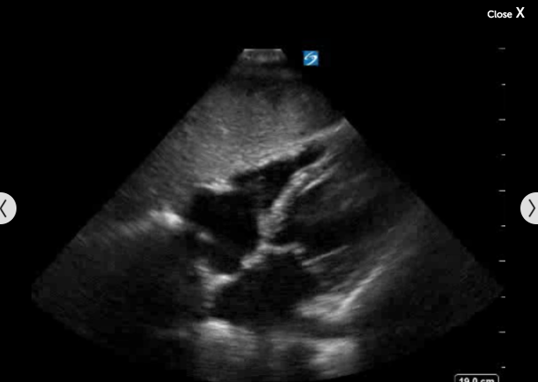

心脏剑突下心包积液图像